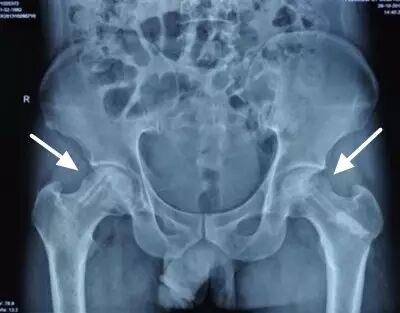

II期和III期的患者治疗方法相同,因为此时股骨头虽然还没有变形,暂时还不需要行人工关节置换术,但是股骨头已经出现空洞,随时股骨头就会塌陷变形,所以单纯的股骨头减压术是不能达到治疗效果的。这时就需要在股骨头减压的同时,植入一根支撑棒,顶住股骨头空洞区,防止股骨头在负重的情况下过早塌陷。其他治疗同之前相同,口服以上药物,定期复查,密切观察病情发展,尽量避免重体力劳动和爬山爬楼。

以上为股骨头坏死减压加支撑棒植入术示意图和术后X线片